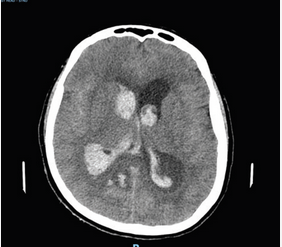

A 60-year-old woman presents with the acute onset of headache. The initial CT scan is shown (Figure 1). An external ventricular drain (EVD) is placed. Which intervention has been shown to decrease the risk of mortality?

Intracerebral hemorrhage with predominant intraventricular hemorrhage (IVH) has been a challenging disease because the expectations of providers and the real outcomes are often discordant. Because IVH affects a fluid-filled space as opposed to the parenchyma of the brain, the expectation is that the patient should recover without significant sequelae. This is clearly not the case; a study using the control populations of other studies with EVD placement and BP control showed mortality rates of 56%. In practice, the reasons for the increased mortality include poor consciousness due to the intracerebral hemorrhage component, recurrent complications from hydrocephalus in ventricular fluid diversion, and complications of ICU care. Studies using fibrinolytics to remove blood have shown improvement in mortality.

The most recent development in the treatment of IVH has been the administration of tissue plasminogen activator (tPA) into the cerebrospinal fluid to aid in the dissolution of blood clots, allowing for drainage of unclotted blood from the ventricles. This technique was first pioneered using streptokinase; now tPA is favored due to the ease of use and suspected improved safety. Interestingly, multiple studies have shown improved mortality with the use of tPA. Skeptics worry that the improved mortality leaves more patients with a poor neurological outcome. The most recent randomized trial, CLEAR III, shows that in the group of patients with >20 mL of intraventricular blood in whom 85% of the blood can be cleared from the ventricular space, functional outcome is also improved. For this reason, the patient described is in a group that would benefit by improved mortality but also improved outcome.1234